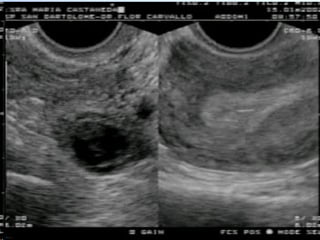

ULTRASONOGRAFIA ECOGRAFÍA ABDOMINAL. ECOGRAFÍA  TRANSVAGINAL. ECOGRAFÍA DOPPLER

Ecografía : Visualización embarazo intrautero  temprano reduce probabilidad  de Embarazo ectópico. Heterotópico: 1/39000 - 1/2100   (en embarazo  con inducción  de  ovulación: 2.9%) El hallazgo ecográfico de hemoperitoneo es mas predictivo de embarazo ectópico que la Culdocentesis.

Todos los embarazos intrauterinos viables deben ser visibles ecograficamente con una hCG sérica de 2000 mUI/ml o mas. La ecografía transvaginal antecede en una semana a la ecografía abdominal en la detección de una gestación intrauterina La ecografía transvaginal con Doppler color detecta las masas anexiales mejor que la ecografía transvaginal convencional.

20% de los embarazos ectópicos, útero y anexos pueden ser normales en la ecografía abdominal “ Aunque la posibilidad de un embarazo ectopico es improbable, no puede ser totalmente excluido”

¿ Cuales es el rol del US TV?  Identificar el saco gestacional Identificar EE > 3.5cm  Identificar actividad cardiaca anexial

¿Cuales son los hallazgos ecográficos? Útero Endometrio engrosado Diminutos quistes dentro de la decidua Interfase hipoecogénica por debajo de la decidua Seudosaco gestacional Miometrio pobre vascularización Endometrio decidualizado con pobre vascular.

Anexos Asa redondeada parauterina de 1 -3 cm Área hipoecogenica rodeada de un anillo ecogenico de tejido trofoblastico y estrato muscular Saco vitelino Estructura hipoecogénica excéntrica, rodeada de un anillo de tejido ovárico Ectopias viables y cuerpo lúteo muestran un anillo vascular rodeando un centro hipoecoico. Peritoneo Liquido intraperitoneal(hemorragia, ruptura) Gran cantidad de liquido i. >>> Ruptura

La ecografía en combinación con los análisis de Beta -HCG permite el diagnóstico definitivo del embarazo ectópico